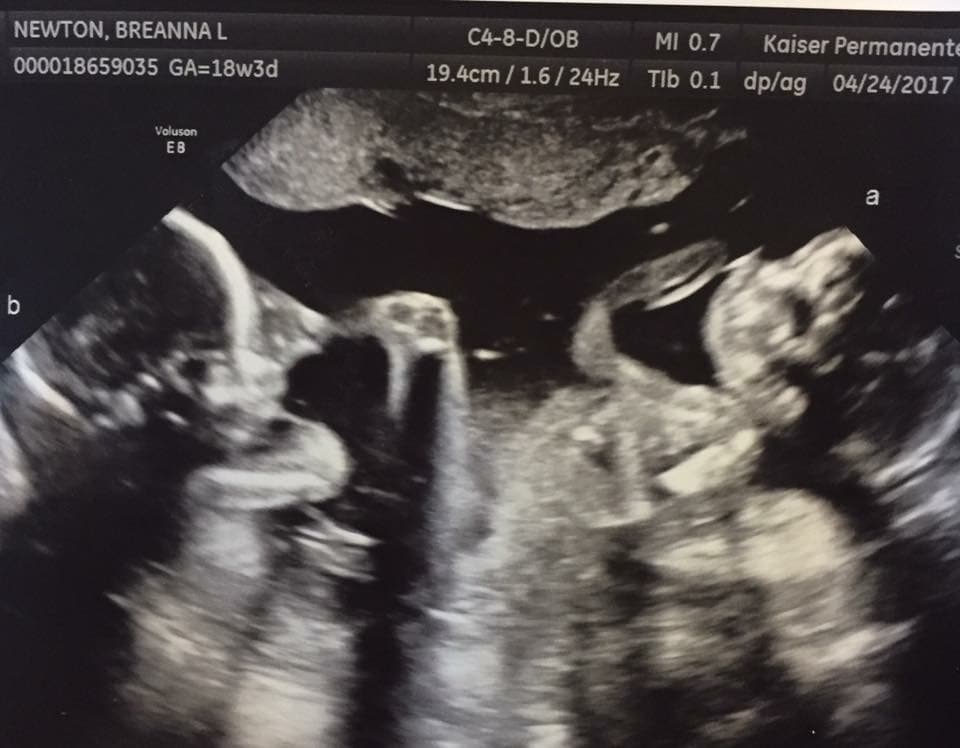

Ultrasound Photos at 18 Weeks Pregnant With Twins